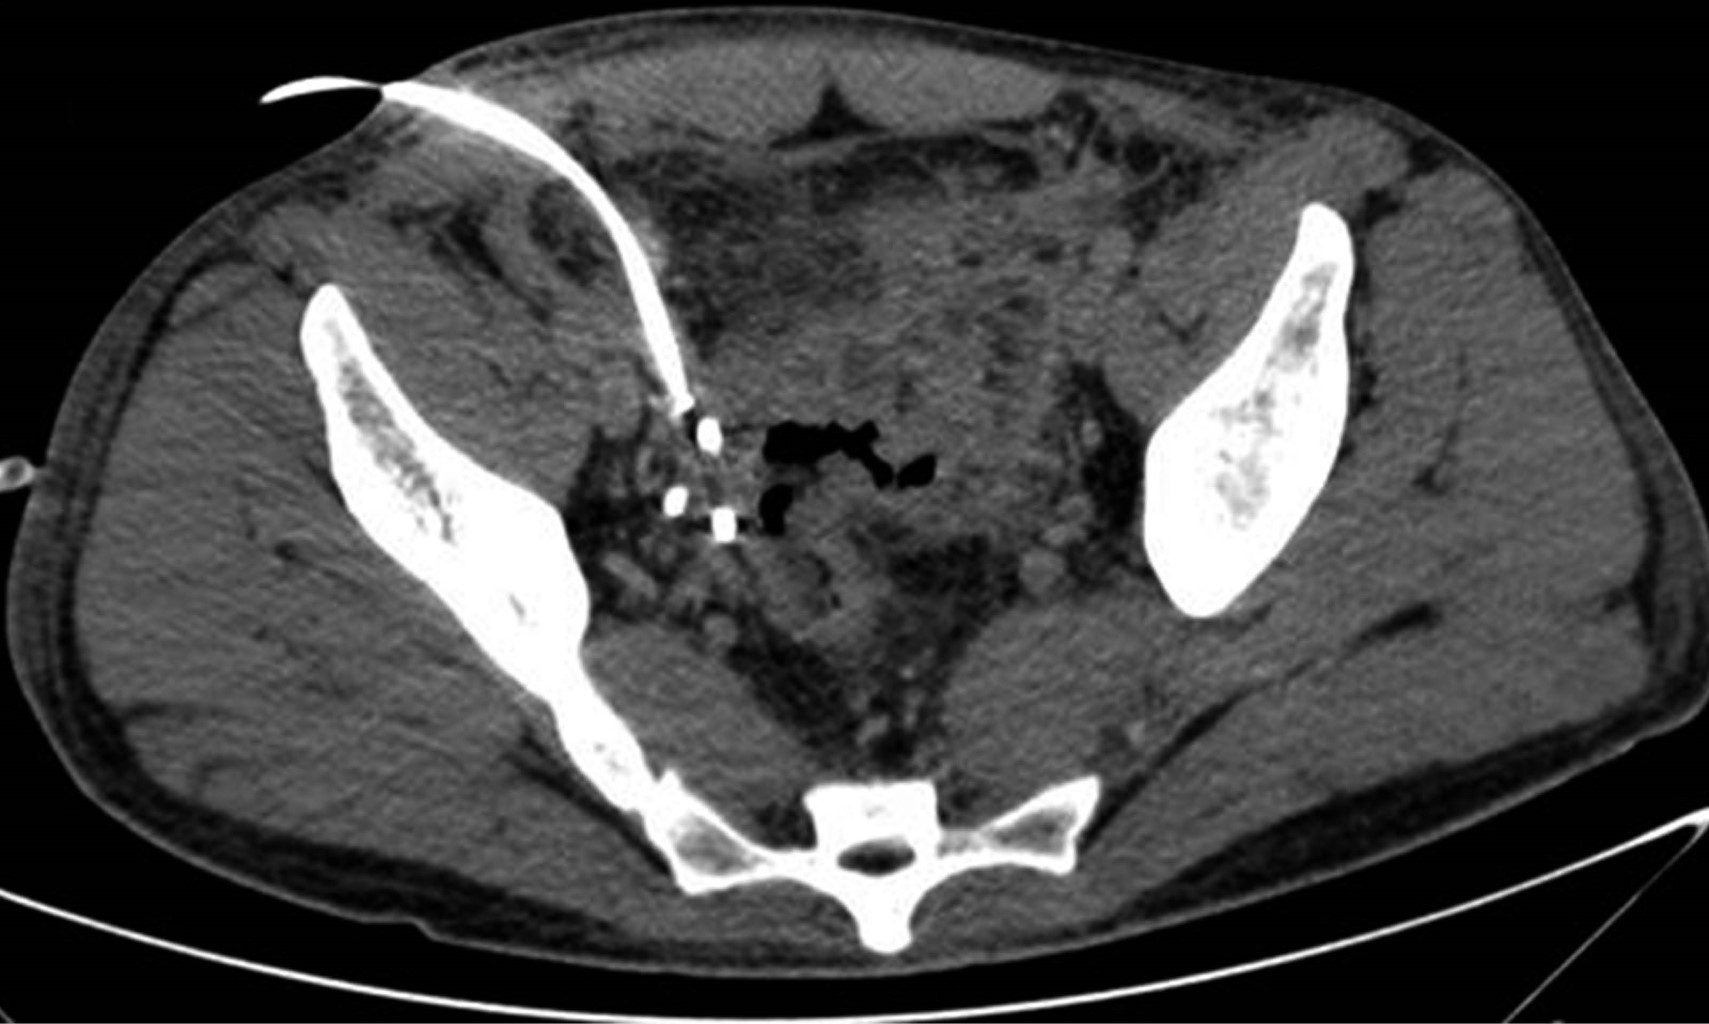

La tomografía de abdomen y pelvis con contraste iv demostró líquido libre en corredera parietocólica derecha, interasa y pericecal. Apéndice cecal con diámetro de 14 mm además de engrosamiento y realce de su pared. Colección supravesical con extensión a fosa iliaca derecha que mide 55 × 75 × 41 mm con un volumen calculado de 88 cm3 (Figura 1) y otra en fondo de saco con extensión a fosa iliaca izquierda que mide 60 × 57 × 70 mm con volumen de 125 cm3. Se decidió punción guiada por ultrasonido con control tomográfico de ambas colecciones (Figura 2), drenando 70 y 120 cm3 purulentos respectivamente. Se dejaron dos drenajes tipo Dawson Mueller® 10.2 fr, uno en fosa iliaca derecha y otro en fondo de saco. Se inició manejo antimicrobiano de amplio espectro con meropenem 1 g iv cada ocho horas y vancomicina 1 g iv cada 12 horas, se dejó en ayuno dos días y se inició apoyo nutricional parenteral durante tres días con oliclinomel®. El cultivo aeróbico desarrolló Streptococcus constellatus sensible a ertapenem, por lo que se cambió cobertura antimicrobiana a base de ertapenem 1 g iv cada 24 horas y vancomicina. El paciente se mantuvo clínicamente estable, sin datos de respuesta inflamatoria sistémica y disminución progresiva del dolor abdominal. Una TAC de control en su tercer día (Figura 3) demostró una disminución importante del líquido en el interior de las colecciones. Se retiró el drenaje derecho en su cuarto día, con un gasto total de 10 cm3; los marcadores inflamatorios presentaron una disminución progresiva durante su estancia, egresándose con 9.9 10^3/μl leucocitos, seg 67%, bandas 0 % y PCR 4.05 mg/dl. Se retiró el drenaje izquierdo previo a su egreso en el noveno día de estancia con un gasto total de 82 cm3. No se realizó apendicectomía de intervalo en el seguimiento debido a que, basado en la edad, los antecedentes y los estudios de imagen al diagnóstico, la probabilidad de neoplasia se consideró baja de acuerdo a las recomendaciones existentes en la literatura.

Figura 1